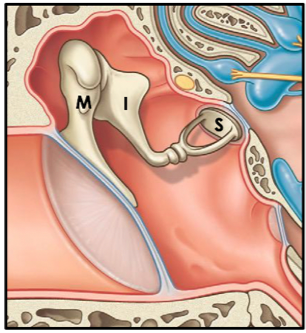

What are the ossicles? Names?

3 bones of the middle ear are the auditory ossicles that link the tympanic membrane to the oval window of the internal ear.

- Malleus (most lateral)

- Incus

- Stapes (most medial)

Which ossicle is in contact with the middle ear?

Stapes